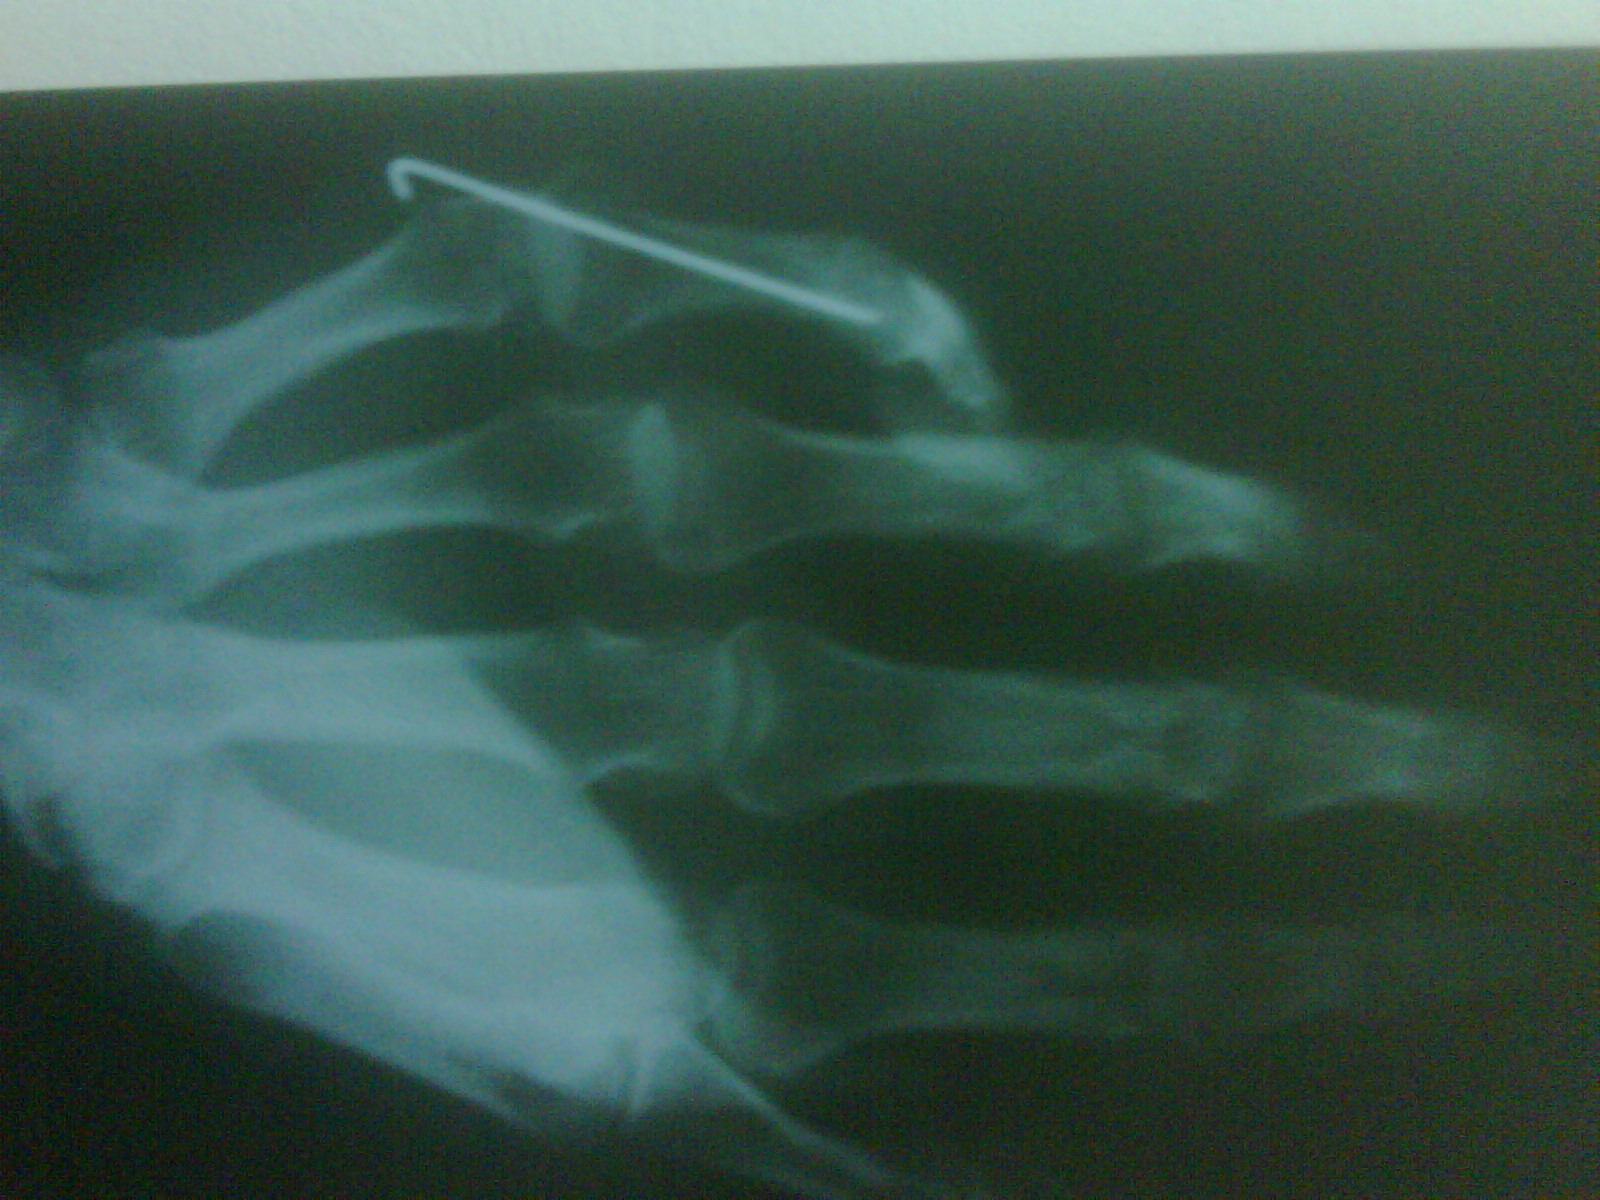

I need a bit of an opinion on a medical problem, I broke my small finger in the first bone just after the first joint, first time they plastered it and it was starting to set at like 45 degrees, so they put a wire in as shown in the xrays.

Now I have about 10 degrees flexion in each joint (all 3), this has been about 3 months now, the xrays taken today and pictures show you whats going on clearly enough where there is deformity in the first bone.

Thanks for the input, the axis of the small finger is like 30 degrees off to where it should be affecting all three joints and the next finger too, have broken more glasses from the weakness and habit of picking stuff up with out thinking.